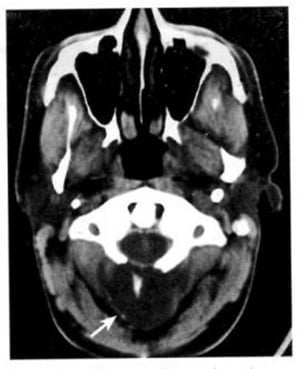

Hình 1.65. U mỡ. Khối u mật độ mỡ, không bắt chất cản quang, lồi vào trong lỗ chẩm từ phía sau (mũi tên). Nó chứa một đốm vôi trung tâm.

1.12. U mỡ (Hình 1.65)

Dấu hiệu XQCTĐT:

– Tổn thương mật độ mỡ, không bắt chất cản quang, nằm ở góc cầu tiểu não hoặc tiểu não.

– Đóng vôi viền hoặc lốm đốm trung tâm và tăng quang.

– Không phù.

Chú giải:

– Hiếm. Thường không có não úng thủy do tắc nghẽn.